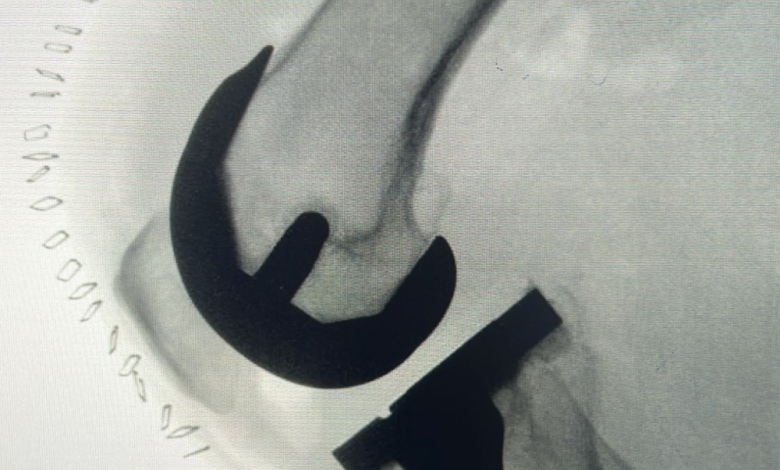

أوضح الدكتور صالح المطلق، مدير مركز جراحة العظام والعمود الفقري بمدينة الملك سعود الطبية، تفاصيل هذه الحالة المعقدة. وأشار إلى أن المريض كان يعاني من خشونة متقدمة ومزمنة في مفصل الركبة، وهو مرض تنكسي يؤدي إلى تآكل الغضاريف، مما أثر بشكل بالغ على قدرته الحركية وأعاق ممارسته لأنشطة حياته اليومية بصورة طبيعية. وأكد الدكتور المطلق أن التدخل الجراحي الدقيق اعتمد على أحدث التقنيات الطبية العالمية ضمن مسار «برنامج جراحة اليوم الواحد» للمفاصل الصناعية.

تكللت العملية الجراحية بالنجاح التام بفضل الله ثم بكفاءة الفريق الطبي. وقد تمكن المراجع من الوقوف والمشي بثبات دون الشعور بأي ألم، متخلياً تماماً عن الحاجة لاستخدام الوسائل المساعدة المعتادة مثل العكازات أو المشايات. ولفت الدكتور المطلق إلى أن سرعة الاستجابة العلاجية مكنت المريض من استعادة وظائف الركبة الحركية ومغادرة المنشأة الصحية في غضون ساعات قليلة من إجراء الجراحة الدقيقة، وهو ما يمثل نقلة نوعية في تجربة المريض.